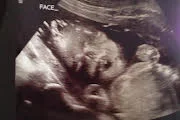

• the fetal period ( week 9 - birth)

the fetal period ( week 9 - birth)

milestones:

- reflexes start to appear and fetus starts moving legs and arms

- 3rd month you're able to see sex

- finger nails, hair, and eyelashes grow